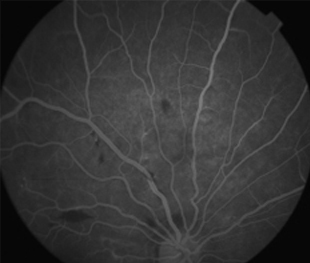

Angiografía OI

- Angiografía: teñido arterial, escape capilar, más tardíamente, no perfusion arteriolar y venular con teñido de las paredes vasculares y dilatación venosa.